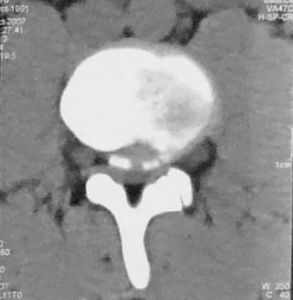

纖維軟骨鈣化本病多採用影象學的檢查方法,其表現主要有以下幾個方面:

1、軟骨鈣化

最常受累的部位是膝、腕、恥骨聯合、肘和髖。受累軟骨包括纖維軟骨和透明軟骨。

(1)纖維軟骨鈣化:最常受累的是膝關節的半月板、腕關節的三角軟骨盤、恥骨聯合、椎間盤的纖維環以及髖臼唇和肩胛盂唇;還可累及肩鎖關節和胸鎖關節的墊盤。纖維軟骨的沉著物,表現為增厚、粗糙和不規則的緻密區,特別是在關節腔的中部。

(2)透明軟骨鈣化:可發生於很多部位,但最常位於腕、膝、肘和髖關節。這些沉著物較薄,呈線樣,平行於鄰近的軟骨下骨。